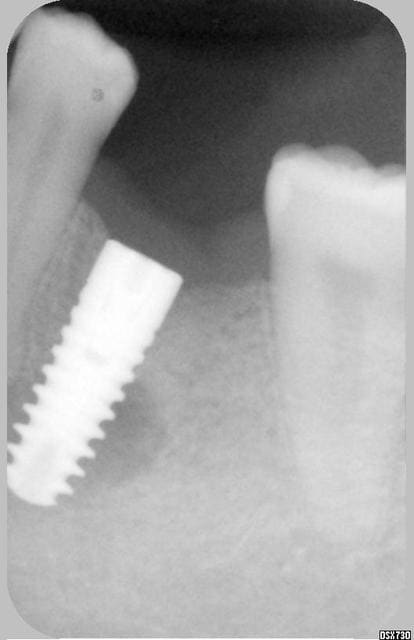

Je revois la patiente aujourd'hui et voila la radio: l'image suspecte a disparu presque complètement, implant complètement silencieux et fixe... todo isso e muito bem!!!

Y'a quand même un tissus fibreux non osseux, mais l'implant a suffisament d'os ailleurs autour de lui pour tenir le coup quand même.

oui Chicot mais s'agit il de fibres ou d'os moins dense ? les limites ne sont plus nettes comme au début.